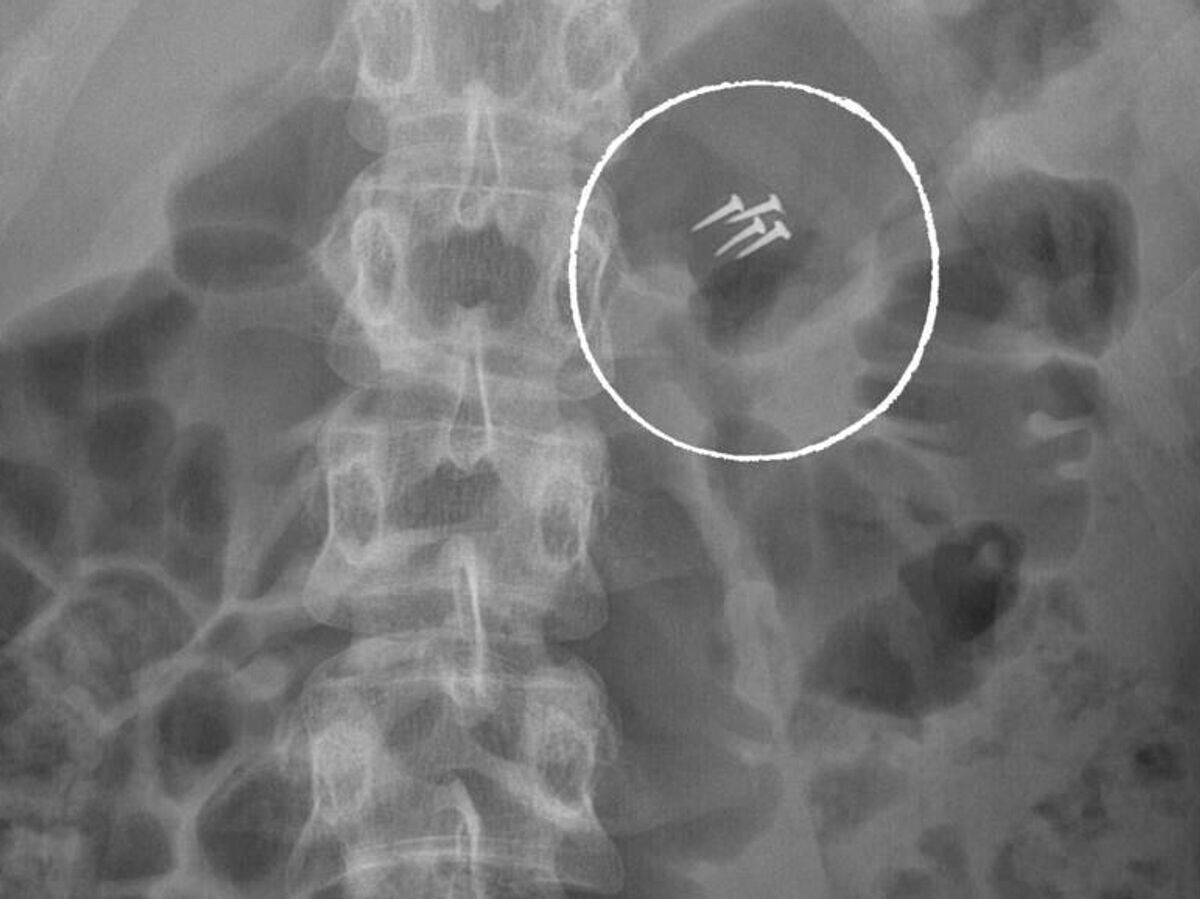

НИИ имени Склифосовского опубликовал подборку самых неожиданных "находок" в пациентах за прошедший год. "Специалисты удаляли беспроводные наушники, украшения и даже гвозди, зажатые в зубах и ненамеренно проглоченные в процессе ремонта", — говорится в Telegram-канале учреждения. В институте напомнили, что ежегодно туда поступают десятки людей с инородными телами, которым требуется экстренная помощь и, чаще всего, длительное лечение. Еще больше новостей в телеграм-канале РИА Новости >>

Гвозди и не только: эти находки в россиянах поразили врачей